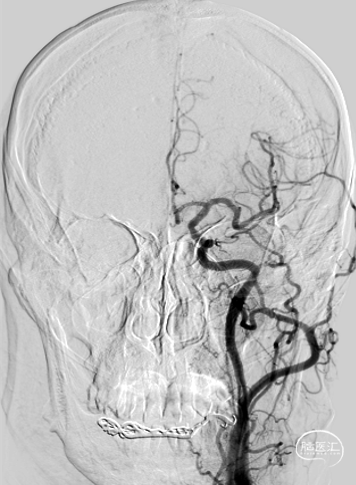

术前影像

左右滑动切换图片

根据3D造影,选取最佳工作位角度。